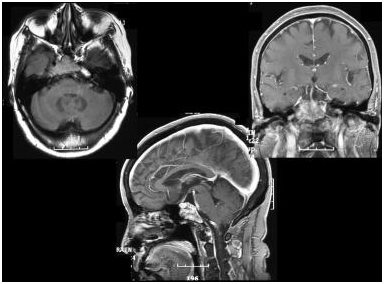

颅底肿瘤是一组具有不同临床意义的组织学类型。较近的手术技术的进步,现在允许顺利切除这些肿瘤与可接受的发病率。过去,颅底肿瘤(SBNs)的研究主要集中在传统的终点,如肿瘤切除的完整性、对辐射的反应、生存率和局部控制。较近,研究人员已经开始欣赏的生活质量(QOL)结果的重要性,是在设置颅底手术的患者和外科医生现在承认的重要性考虑不仅治疗生存的影响,而且手术后病人的福祉。这对SBNs患者相关,因为这些肿瘤的治疗通常涉及广泛的手术,无论辅助放疗或不辅助放疗,都可能具有毁灭性的发病率和毒性。

颅底脑膜瘤患者的生活质量

Mohsenipour等较近的研究表明,脑膜瘤切除后大部分患者的整体生活质量有轻度至中度的损害,但在生理障碍和能量水平域存在严重的损害。类似的结果也见于涉及海绵窦的脑膜瘤。在另一项研究中,105名患者的结果后的岩斜脑膜瘤切除标准侧颅底的方法是使用, 76%的患者报告好在术后1年慢慢康复,但72%的患者仍功能低于公认的准则。

术后生活质量的稳定性是关系到患者整体生活质量和康复质量的重要问题。前颅底手术和海绵窦脑膜瘤切除后对生活质量的时间评估显示,术后一年生活质量逐渐好转,二年评分稳定。然而,在颅内肿瘤患者术后期间,生活质量逐渐恶化。年龄对前颅底肿瘤或海绵窦脑膜瘤切除术后健康相关生活质量有负面影响。